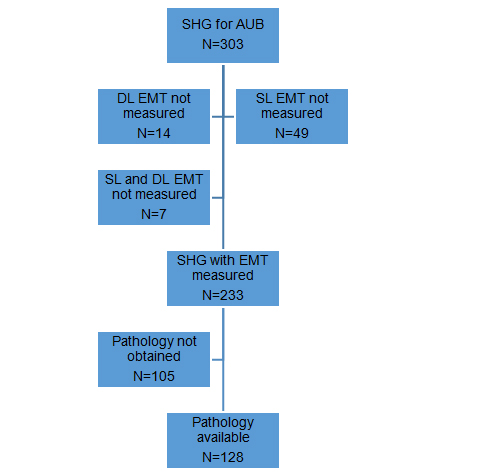

Sonohysterographic Measurement Of Endometrial Thickness .